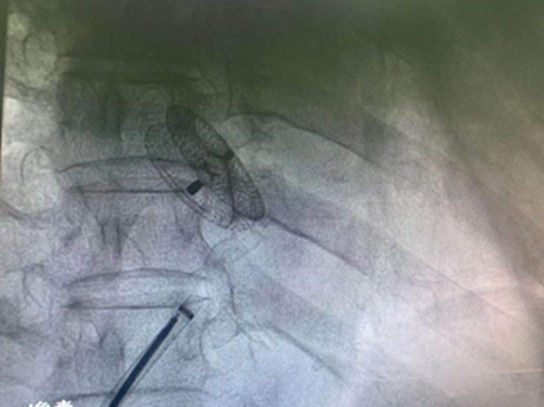

释放后的封堵器

小然今年33岁,自幼常有偏头痛,没有在意。直到半年前的一天夜里,头痛难忍的小然到当地医院急诊就诊,在排除了导致头痛的其他疾病后,完善心脏彩超发现房间隔缺损(II孔型),在他的房间隔上多出了一个宽度约11.3mm的洞,这个多出来的指甲盖大小的“心眼”就是导致他这么多年头痛的罪魁祸首! 在当地医院的推荐下,小然慕名来到首都医科大学附属北京佑安医院心血管内科,经过评估,李艳兵主任决定为其进行房间隔缺损封堵术。术前,介入团队会同超声科认真研判患者病情,制定手术方案.当晚,在超声科丁蕾医生的全程辅助下,心内科介入团队将“补心”工具——封堵器,经鞘管送至房间隔缺损位置。随着封堵器的释放,房间隔缺损被成功封堵,复查超声结果提示左右心房分流消失,手术成功完成,全程用时不到1小时。